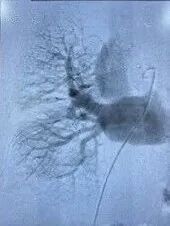

追加注入肝素2000u,于右股静脉交换置入18F鞘管,沿加硬导丝送入腾复血栓抽吸导管于左下肺动脉,行负压抽吸可抽出较多暗红色血栓,送入肺动脉取栓支架系统于左下肺动脉行取栓术,可取出较多暗红色血栓。复查造影提示左下肺动脉未见明显血栓,血流明显改善,测得肺动脉压力下降至40/3mmHg。

取栓中

术后造影

调整导丝至右下肺动脉,再次送入肺动脉取栓支架系统于右下肺动脉行取栓术,可取出较多暗红色血栓。复查造影提示右下肺动脉未见明显血栓,血流明显改善,测得肺动脉压力26/2mmHg。撤出血栓抽吸导管,于下腔静脉造影明确肾静脉位置腰1椎体下缘水平,在肾静脉位置以下成功置入下腔静脉可回收滤器,复查造影示下腔静脉可回收滤器位置正常。